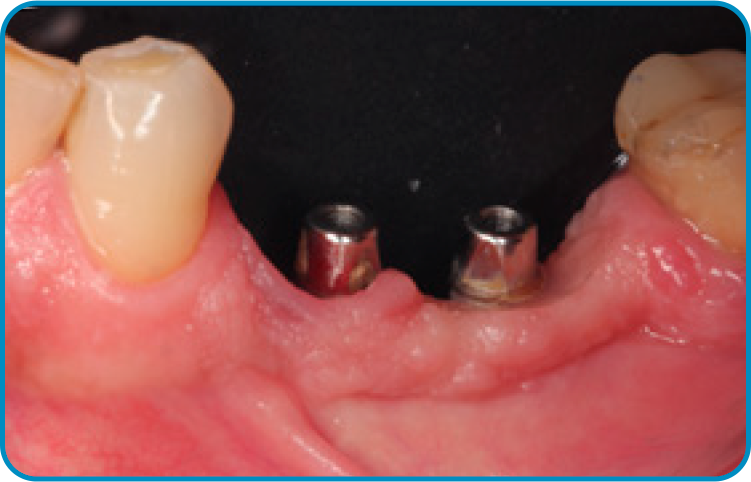

O caso clínico iniciou-se em 2015 com o objetivo de restaurar função e estética. Foram instalados dois implantes nas regiões dos dentes 35 e 36, seguidos pela osseointegração e condicionamento tecidual. As próteses finais foram confeccionadas sobre pilares Arcsys, com ajustes oclusais precisos. O acompanhamento clínico completa dez anos, com exames periódicos e manutenção regular. Observa-se excelente estabilidade óssea e saúde peri-implantar. O caso comprova que protocolos bem executados e componentes de qualidade garantem longevidade previsível.

5 | Imagem radiográfica evidenciando a estabilidade tecidual ao redor dos implantes após dez anos de função.

6 | Aspecto clínico após dez anos de função.